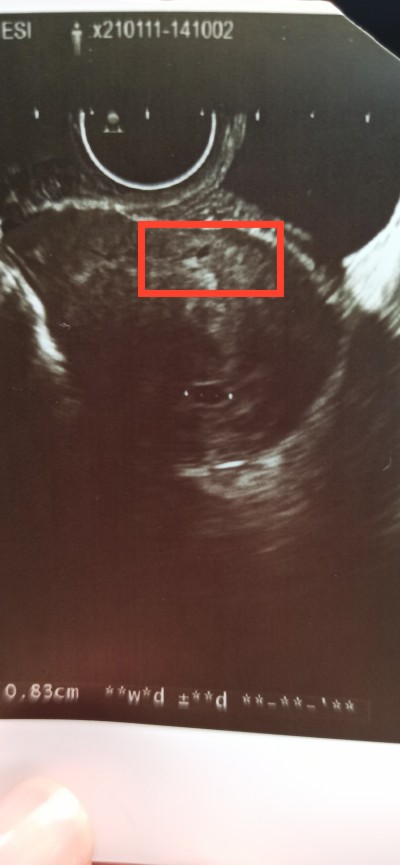

Kırmızı işaretlediğim yer nedir acaba ?image

Bazen ultrasonda öyle boşluklar olabiliyor bak öbür tarafta da var hafiften. Korkma yani . Kanaman falan da yoksa kendini hiçbirşey için strese sokma

Canım keseye yakın olur onlar baya uzakta kanama değil boşluk olarak çıkmış korkma

Hamilemisinn keseye benziyo sanki

Evet yeni hamileyim bebek kesesi noktalı işaretlenen yer

Gebelik var gayette güzel bir kese oluşmuş şimdi bebeğin oluşmaya basliycak ilerleyen haftalarda içerde küçük bir nokta göreceksin

Canım o üç noktalı yer var ya ora kese

Geç döllenmiş sanırım adete göre  5+3 iken usgde 4 anca demişti. Yani şuan 4 haftalık mı 4 mü olcak bilmiyorum net bı açıklamada da bulunmadı. Mercimek kadar daha dedi ama resimde kese dışında bişey görünmüyor :(  önümüzdeki hafta görürüm inşallah